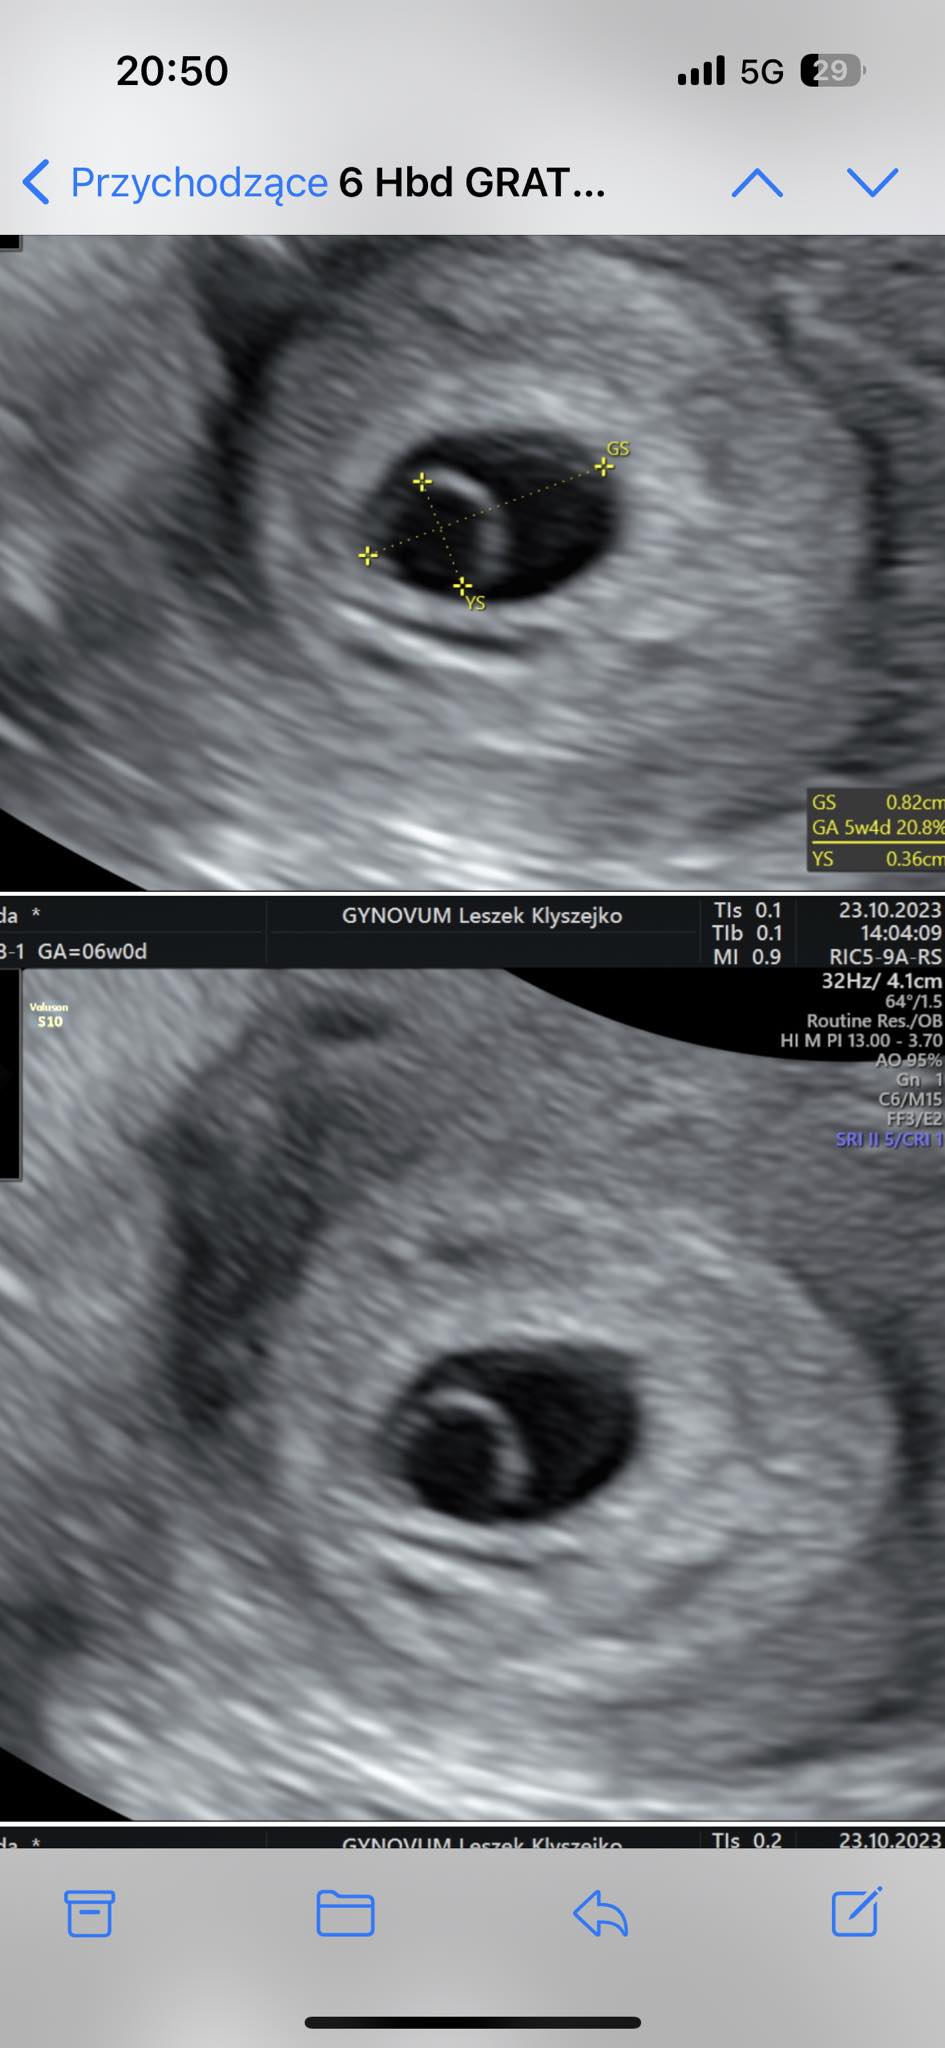

Witam ,jestem w 8vtygidniu viazy ,dzisiaj zaczęłam plamić na brązowo, pojechałam do szpitala tam zbadał mnie lekarz 3 min i powiedział że nam odstawić leki i w środę będzie poronienie,nawet nie zapytał czy na cis choruje a mam policysttczbe jajniki,pokaże wam zdjęciach,jutro może uda mi się spotkać że swoim lekarzem.1 zdhevue jest z orzed 2 tygodni a drugie z dzisiaj wieczorem,czy rzeczywiście coś Sue dzieje? Nie odstawiłam leków,teraz nie plamie.

• received_1396161801324063.jpeg

received_1396161801324063.jpeg

127,2 KB · Wyświetleń: 319